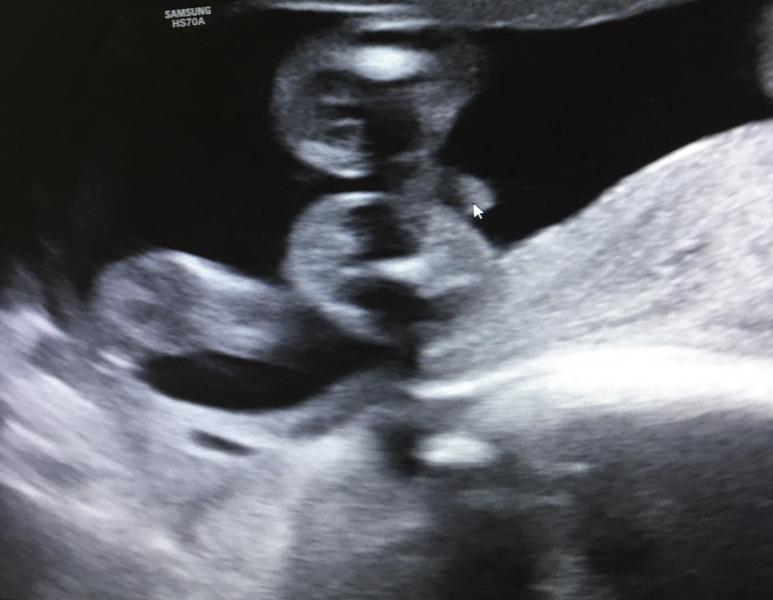

Все приметы, подсчёты и предсказания, как и предположение на первом скрининге оказались не верными😅

Две абсолютно разные беременности и в итоге у нас будет второй мальчик!!!!!